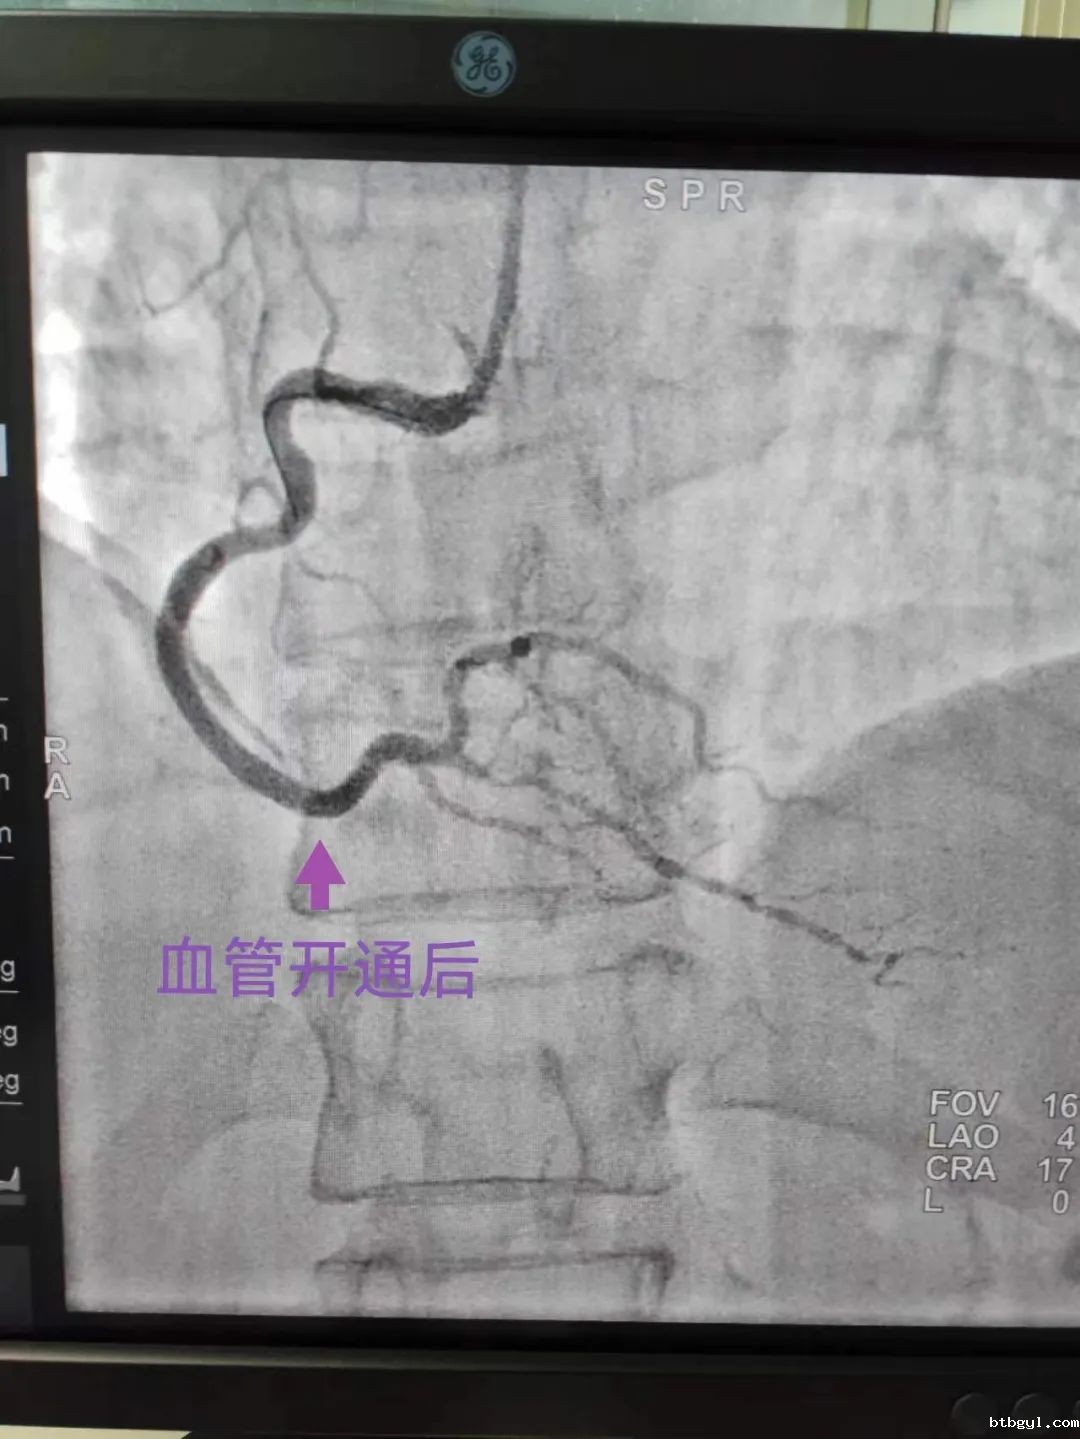

“合江县胸痛中心群”发来信息 胸痛中心协调员迅速回应 11月29日下午4点57分,“合江县胸痛中心群”对话框显示出院前急救医生罗会发出的心电图,并提供简要病史:患者53岁女性患者,有高血压病史,胸痛半小时,心电图提示急性下壁ST段抬高型心肌梗死,目前血压偏低,距离到达医院10分钟车程。 消息立即引起胸痛值班人员的关注,情况危急,患者随时有生命危险!胸痛中心协调员谢勇及医疗总监张永强立即做出回应:患者诊断明确,有行急诊冠脉造影及PCI指征,建议双绕直接送导管室,先负荷双抗药物,预谈话,完善术前准备。 急救车内车外信息共享 各岗位医护人员各司其职 张永强主任通过微信群与随车罗会医生保持沟通和联络,并指导罗会医生,在急救车上尽可能与患者及家属充分沟通病情,如果同意急诊介入手术,可以考虑绕行急诊科、CCU,直接到达导管室。 罗会医生告诉患者随时有突发心血管恶性事件可能,尽早开通血管,才能救活更多心肌,挽救患者生命!时间就是心肌、时间就是生命!目前最快最直接的方法就是器械开通,我院心内科介入团队有充足的能力开通病变血管。 16:58 患者家属口头同意介入手术(17:11签字确认),院前护师给患者顿服阿司匹林300毫克及氯吡格雷300毫克。 16:59张永强主任启动导管室。 CCU病房预留床位、导管室提前激活、心内科手术医生提前到位,接诊工作在患者到达之前全部准备就绪。 17:10 120车驶进医院大门 双绕直达导管室; 17:15谢勇主治医师消毒铺巾并桡动脉穿刺; 17:16 桡动脉穿刺成功并给予肝素抗凝; 17:18开始冠状动脉造影检查。 造影发现,患者优势右冠脉中段闭塞,病情凶险!但术者凭借丰富的手术经验及娴熟的操作技术,根据具体情况制定出对应的手术方案。很快,导管成功到位右冠开口。 17:26经过重重阻碍,导丝终于顺利通过闭塞段到达右冠远端真腔,阻塞的血管重现了血流! 至此,心血管团队创造了心梗患者救治的“奇迹”,D-TO-W时间仅16分钟,这是必威betway西汉姆联官方网站胸痛中心至今的最佳成绩!(之前最佳是双绕急诊PCI,D-TO-W时间23分钟),手术顺利完成,手术医生及护士携带除颤仪将患者护送至CCU。 必威betway西汉姆联官方网站党委书记、胸痛中心主任陈应军在肯定成绩的同时,作了三点要求: 1、急救战线前移,打通胸痛救治最后一公里,让更多高危胸痛病人得到及时的救治; 2、时间就是心肌,时间就是生命。提高双绕比例,缩短D-W时间至60分钟之内,提高救治成功率。 3、继续通过医患微信群、现场义诊、宣教等方式加强民众对胸痛知识的认知度,缩短胸痛发病至就诊时间,降低急性心肌梗死的发病率及死亡率。 这次救治中D-TO-W 16分钟的新突破充分展示了我院胸痛中心过硬的心梗救治能力,同时,也反映了我院胸痛中心在整个合江地区胸痛中心建设推进过程当中的显著成效。 必威betway西汉姆联官方网站是合江地区唯一能全天24小时行急诊PCI的医疗单位。 在院领导班子的正确带领下,胸痛中心运行近两年来取得了长足的进步。随着胸痛中心的建设,各重点科室业务能力得到了提升,心血管介入水平明显提升,救治的危重患者较前增加,死亡率下降。目前今年行急诊PCI近80例,胸痛中心在每位医护人员的共同努力下,2023年行PCI超300例,技术力量及救治水平的不断提高将造福更多的胸痛患者。 在胸痛中心建设的路上我们任重而道远,在前进的道路上必威betway西汉姆联官方网站胸痛中心勠力同心、履职尽责、勇于担当,为合江县人民的健康保驾护航!